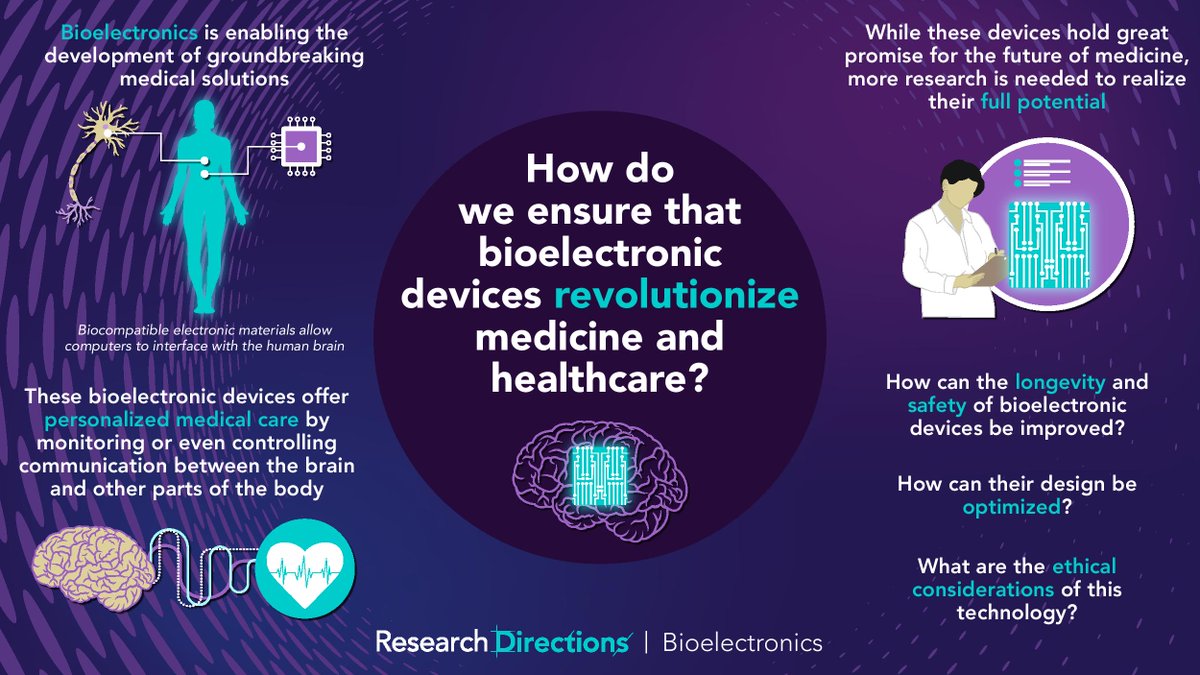

#RDBioelectronics welcomes contributions from researchers to answer this question from @sc_laboratories: 🟣How do we ensure that #bioelectronic devices revolutionize medicine and healthcare? Learn more about this question and how to contribute:cup.org/3pcKJ4o #bionics